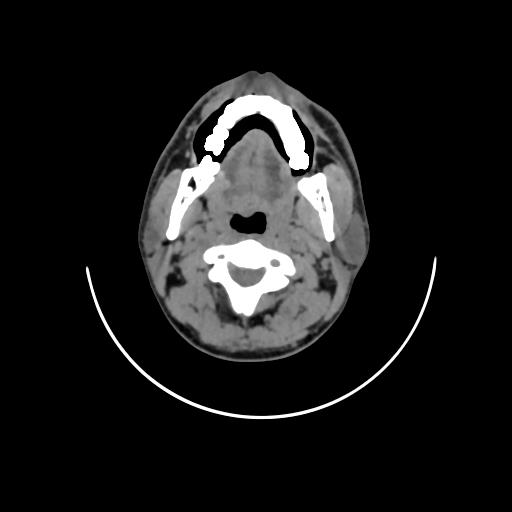

Fig. 1: Non-contrast CT reveals irregular contour of right lateral border of tongue

Computed tomography (fig. 1) changed the nodal staging of 8 patients out of 30. 7 clinically N0 necks were correctly upstaged to N1 later proved by histopathology. 1 was wrongly upstaged to N1, which remained N0 after histopathology.